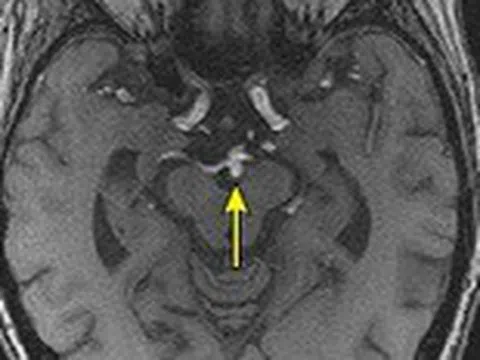

Làm sao để phát hiện phình động mạch não và khi nào cần điều trị?

Phình động mạch não là một tình trạng nguy hiểm được ví như 'kẻ giết người thầm lặng', có thể gây tử vong. Vậy...